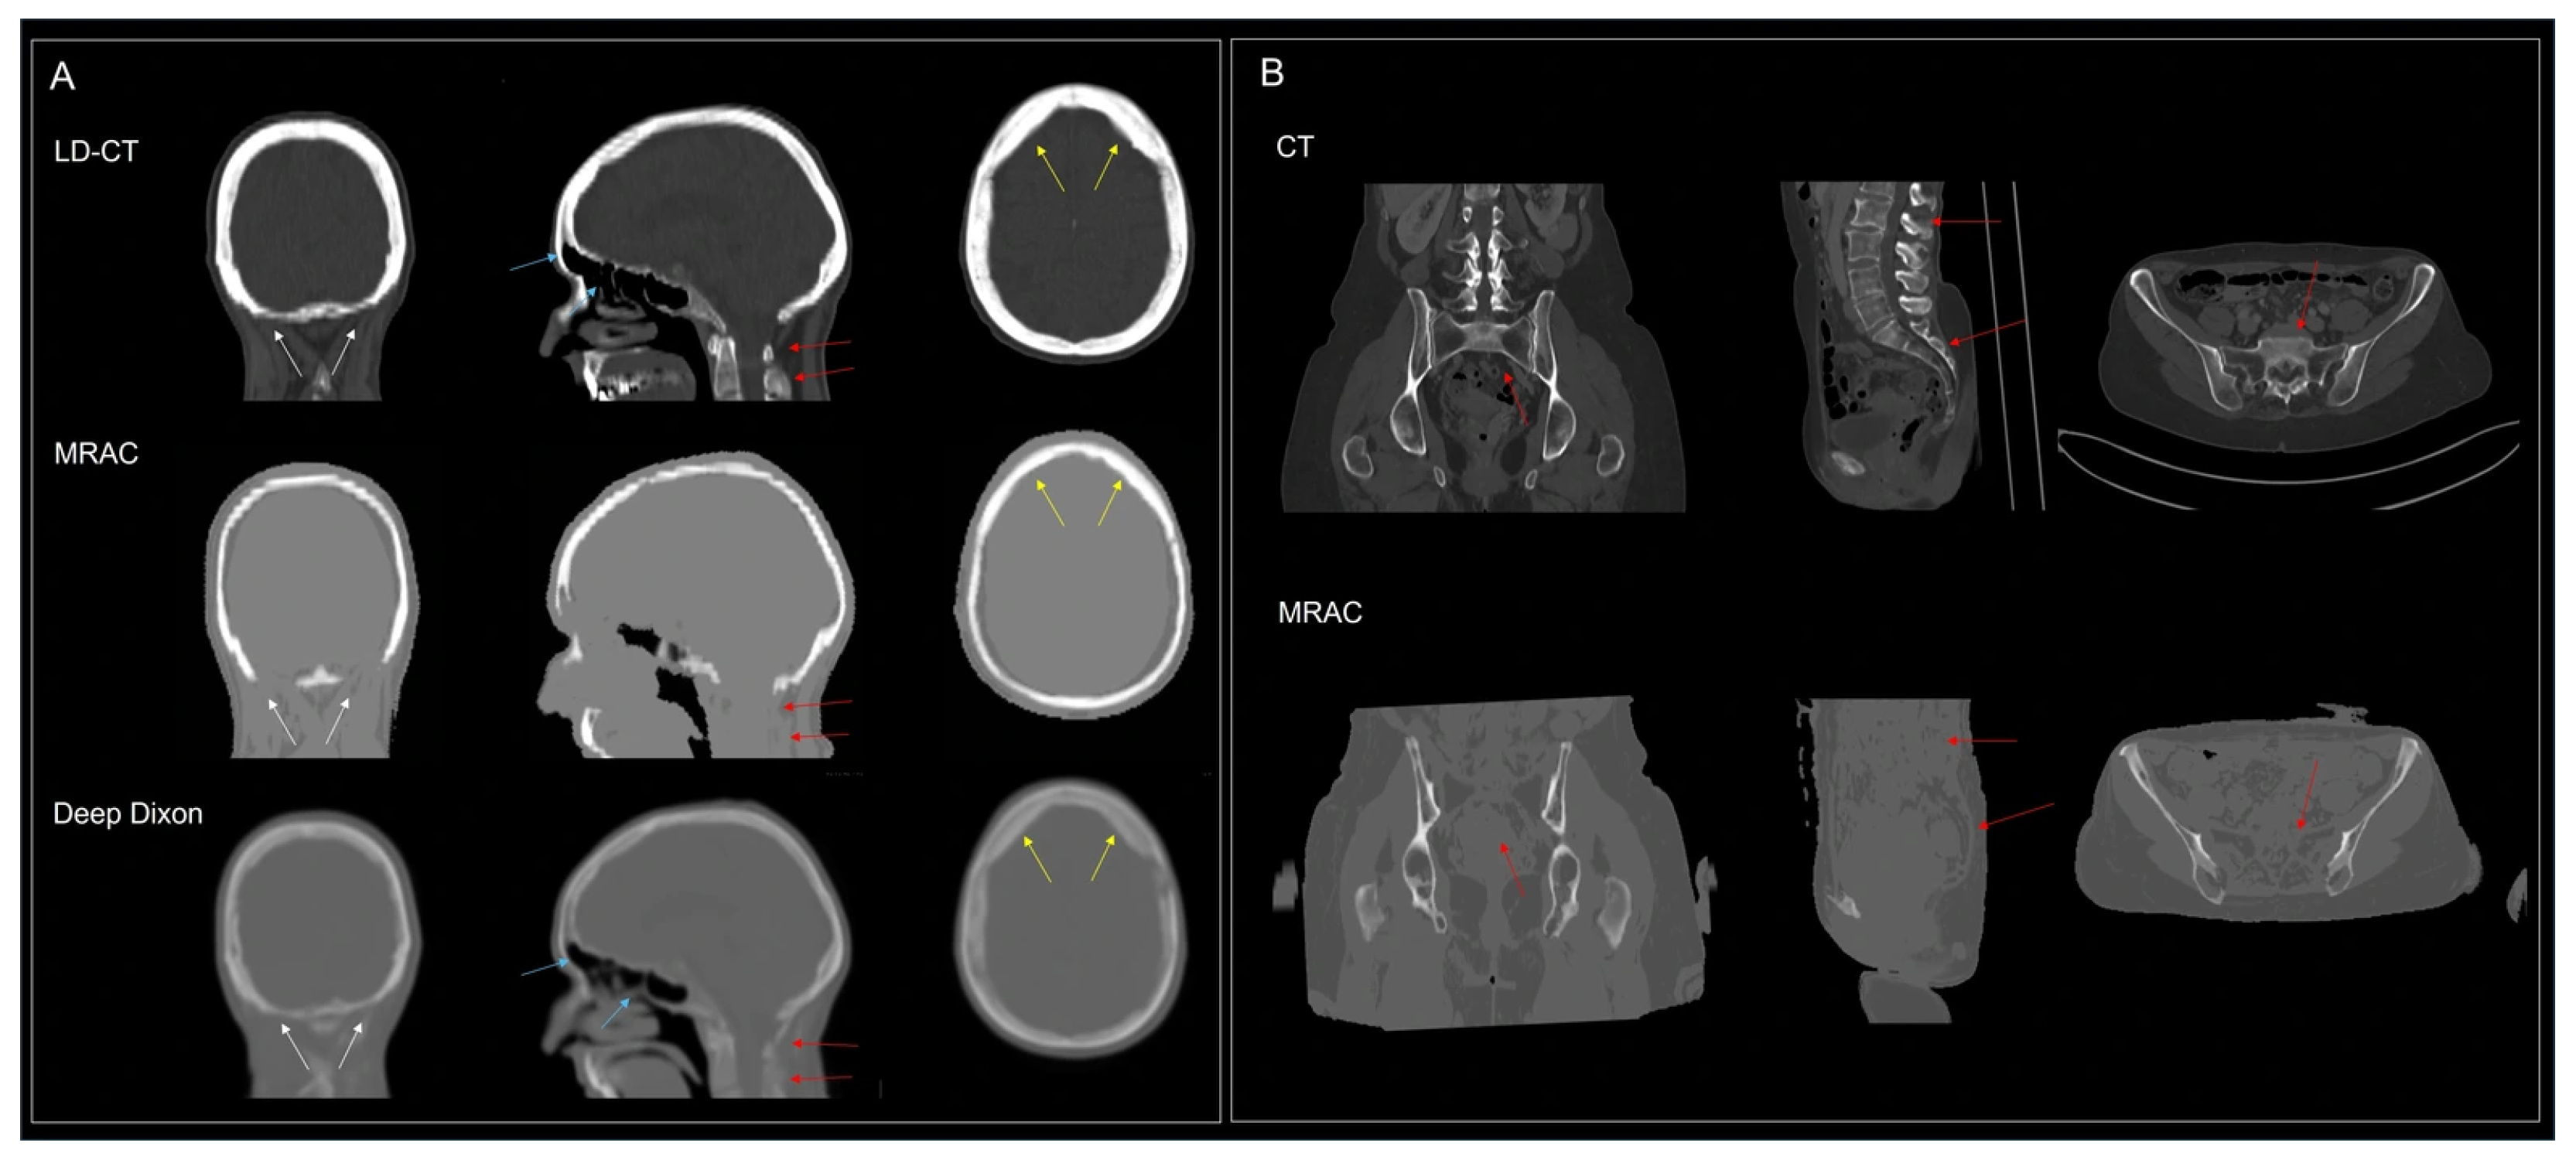

4.3. Brain Applications